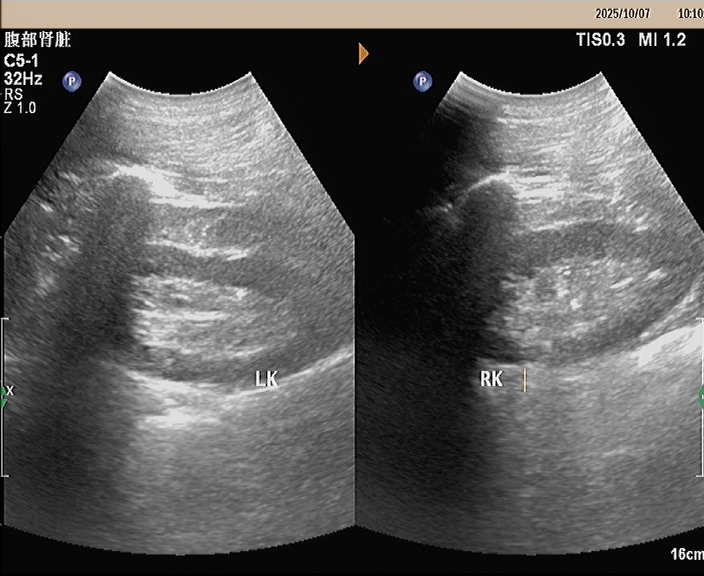

入院经过常规相关检查后考虑肾病综合征,为了进一步明确诊断,2025年10月9日,我院功能科在超声引导下行右肾下极实质穿刺活检术,病理活检:Ⅱ期膜性肾病。经治疗后患者血压控良好,下肢水肿消退,未诉特殊不适办理出院。

指在无菌B超或彩超的定位下,通过局部麻醉,用细小的穿刺针进行局部穿刺,再经光镜和电镜检查,从而做出正确的肾脏病理诊断。因此,为了明确治疗方案、判断疾病预后,医生往往需要对患者进行肾脏穿刺活检术。一旦医生告知患者需要行“肾脏穿刺”,很多患者往往会十分忐忑,认为在肾脏穿刺是一个“很可怕的手术”、“搞不好肾脏会坏掉”。其实肾脏穿刺的针非常细,直径只有1毫米左右,穿刺过程只需要几秒钟,整个过程就10分钟左右,全程医护人员也会陪同并指导配合,并没有想象中的那么可怕呢!